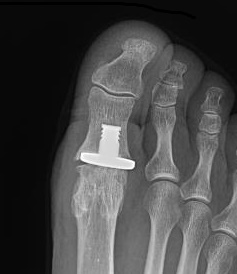

Joint replacement

Options

Hemiarthroplasty

Stryker Cartiva synthetic cartilage implant - recalled due to safety concerns

Total joint arthroplasty

- silastic implants

- press fit metal / polyethylene

Anika Toe Motion Implant System

Stibolt et al Foot Ankle Spec 2019

- systematic review of hemiathroplasty versus total toe arthroplasty

- improved function and ROM with hemiarthroplasty

Cartiva synthetic cartilage implant

Baumhauer et al Foot Ankle Int 2016

- RCT of synthetic cartilage implant versus arthrodesis

- 152 implant patients with 2 year follow up

- 9% revision rate to arthrodesis at 2 years

- similar outcomes to arthrodesis, but with maintenance ROM